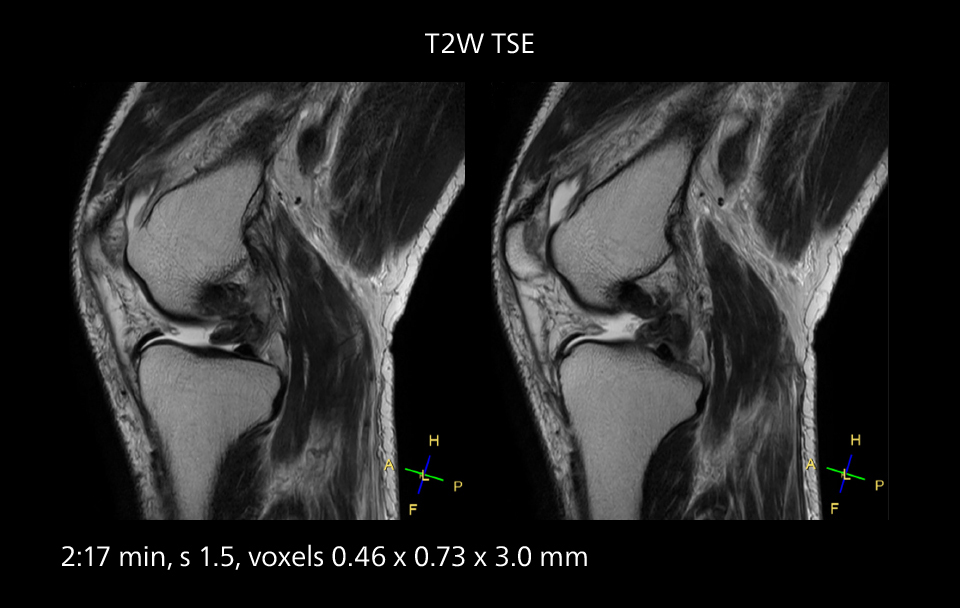

Images showing a posterior cruciate ligament (PCL) tear, a detached medial collateral ligament (MCL) on the tibial side and an intact anterior cruciate ligament (ACL). SmartPath to Elition X helped reduce scan time compared to previous imaging while maintaining resolution.

Overall, imaging time per sequence has been reduced since the Elition X upgrade. This can help reduce the risk of patient movement and the need for rescans. “As our hospital has many elderly patients, we consider it important to obtain high-quality data in a short time,” Dr. Makuuchi says. “Shorter imaging times are also useful for accepting emergency patients, because faster emergency studies have a reduced impact on the daily examinations schedule. In emergency cases it is also important that high quality images are obtained in a short time.”